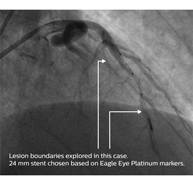

Результаты исследования ADAPT-DES показали, что ВСУЗИ было связано с выбором более длинных стентов1. ВСУЗИ помогает подтвердить области позиционирования стентов от «здоровых до здоровых» участков сосуда благодаря определению объема бляшки и типа ткани на границах поражения.

• 10-миллиметровое расстояние упрощает расчет длины и не требует использования устройства протяжки или маркерного проводника.

• Три рентгеноконтрастных маркера, которые отсутствуют у других катетеров для ВСУЗИ.